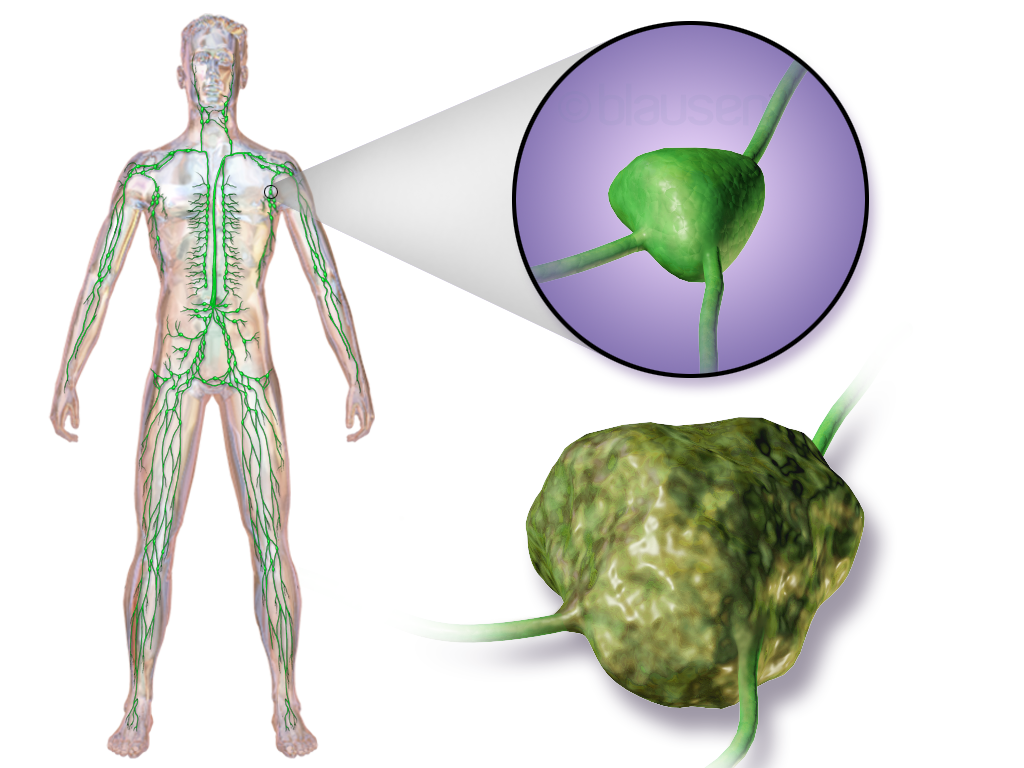

Изображения и схемы: как выглядит лимфа